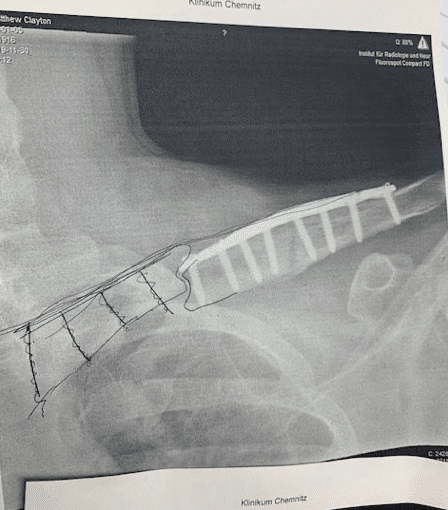

Goerke crashed while jumping through a large triple section and landed extremely short on the jump. The impact of the crash caused the majority of his injuries, fracturing his spine at the L2 vertebrae and broke his left clavicle. He was taken to Klinikum Chemnitz; a local hospital near the Fair where surgeons performed the first of two scheduled surgeries stabilizing his spine with rods. The second surgery to address the left clavicle break is expected to be scheduled this Thursday.